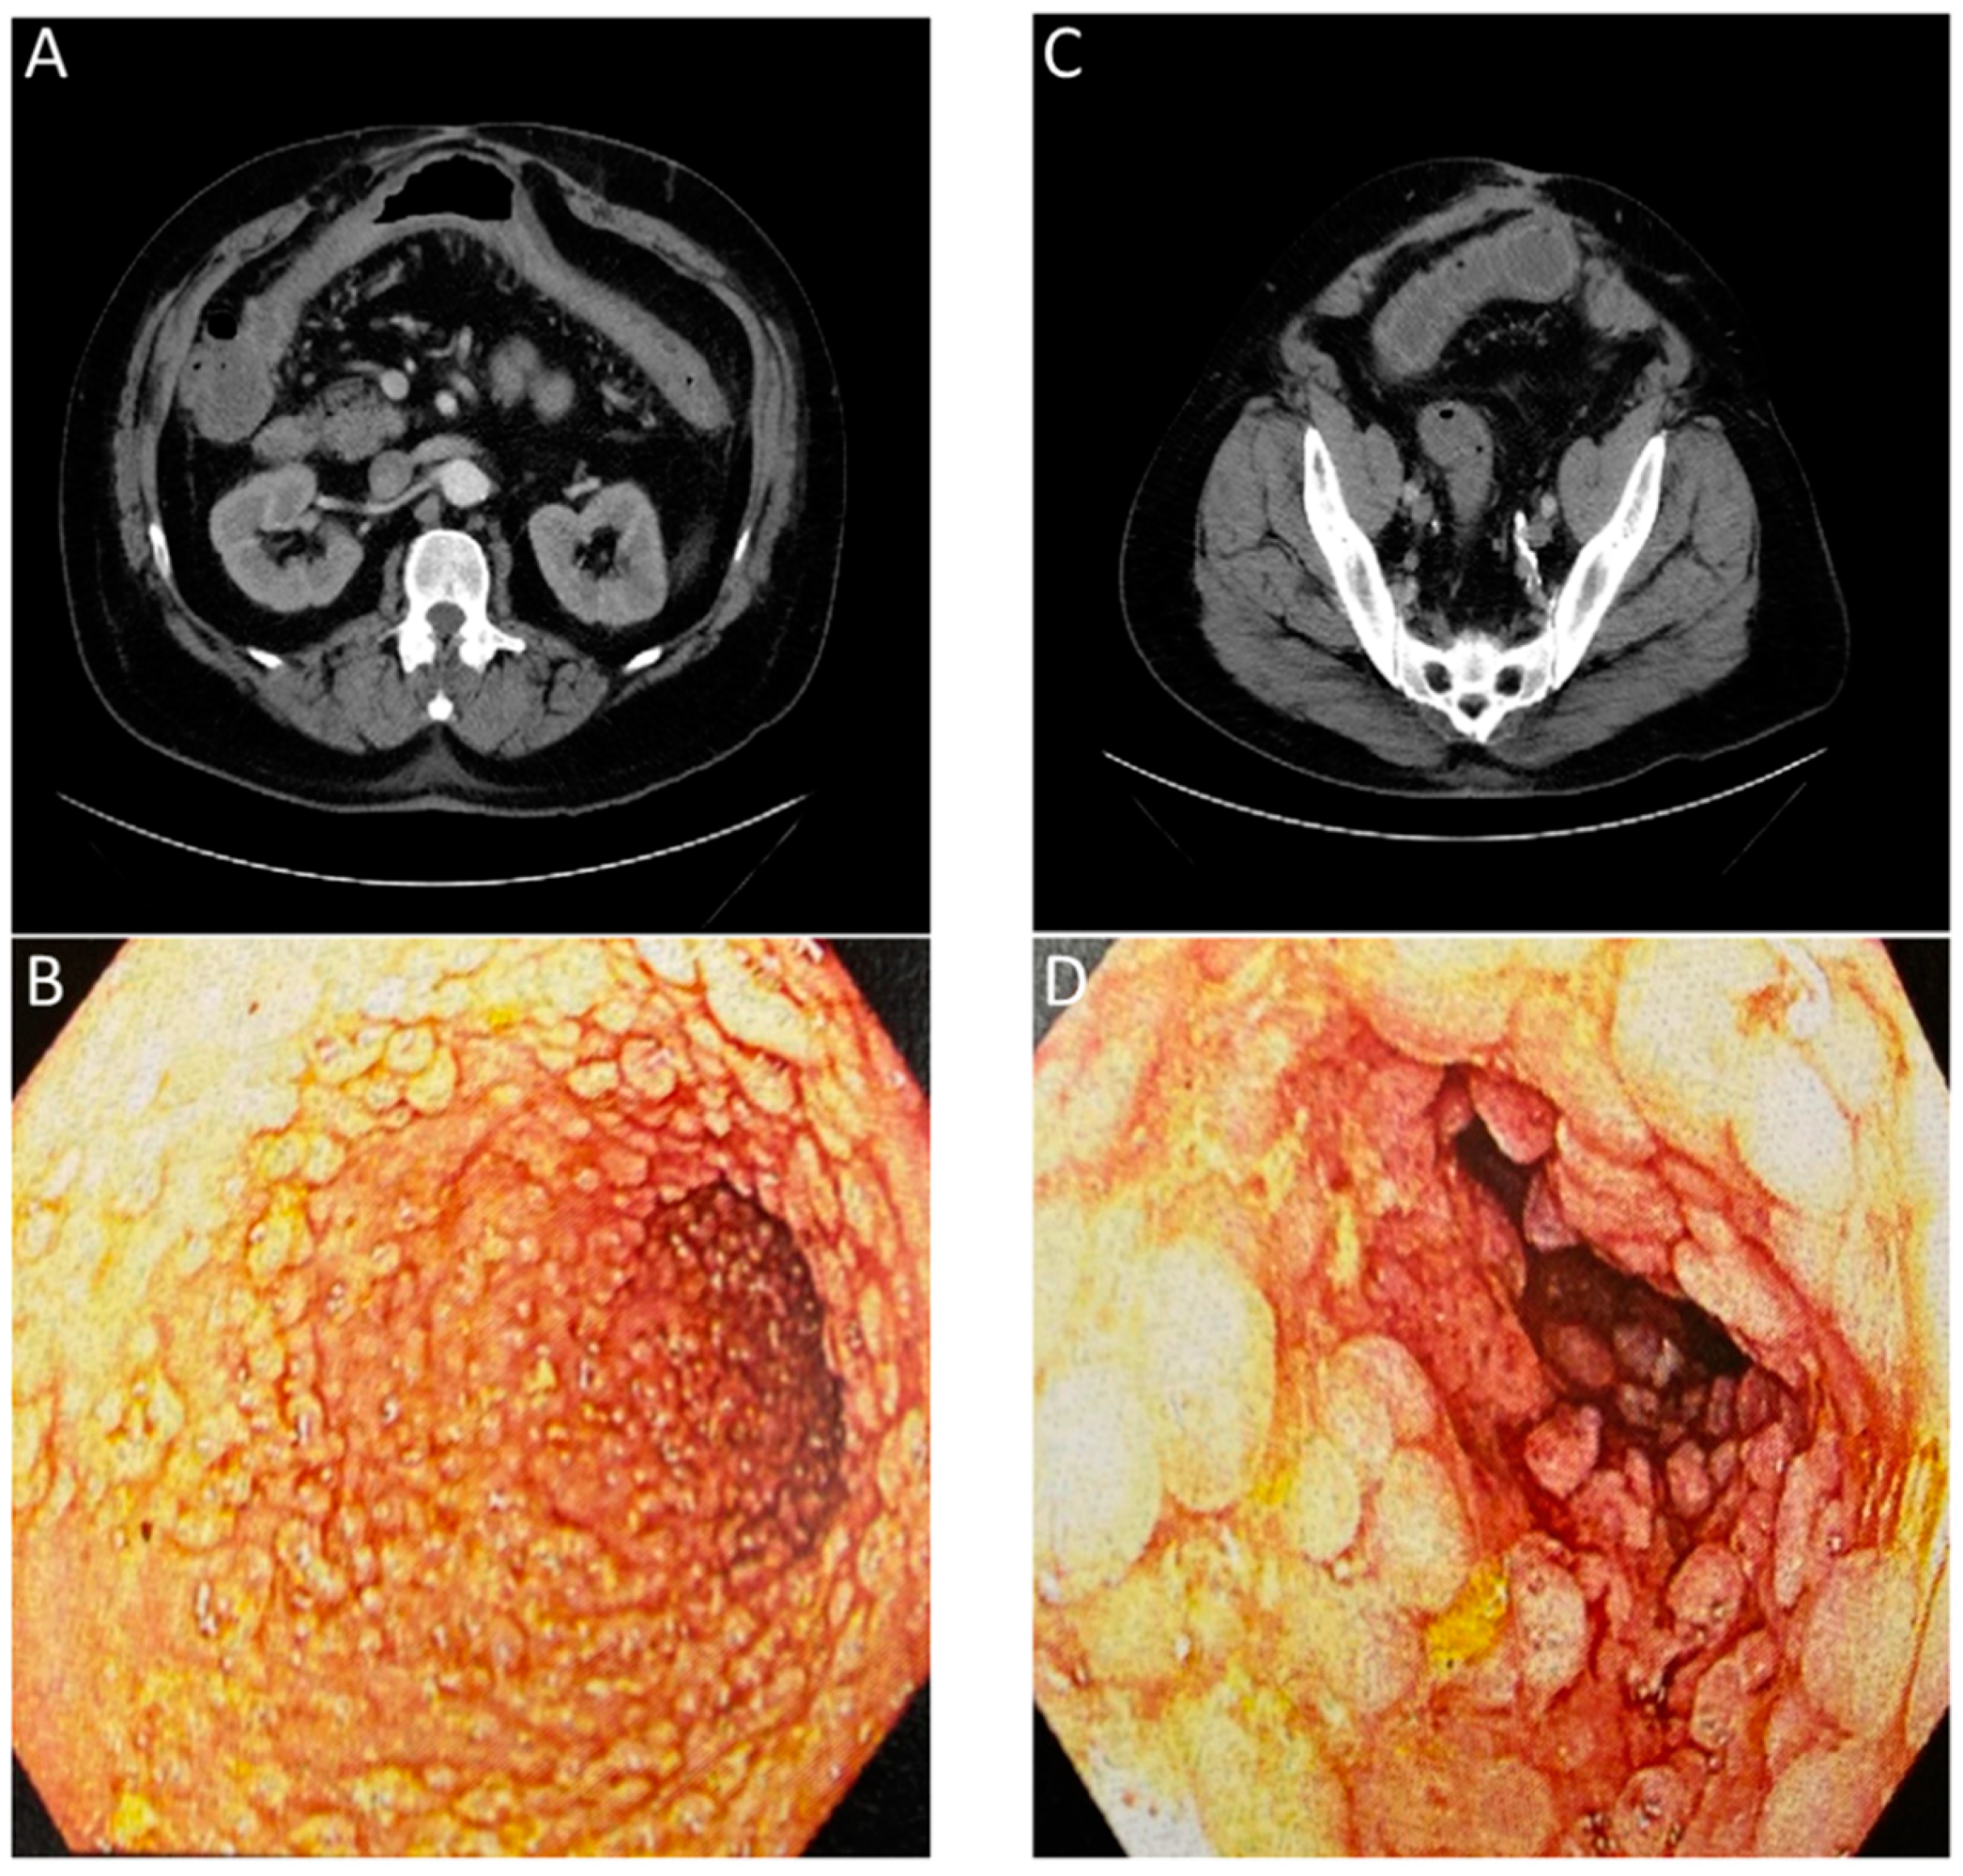

- Catalano, O.A.; Wu, V.; Mahmood, U.; Signore, A.; Vangel, M.; Soricelli, A.; Salvatore, M.; Gervais, D.; Rosen, B.R. Diagnostic Performance of PET/MR in the Evaluation of Active Inflammation in Crohn Disease. Am. J. Nucl. Med. Mol. Imaging 2018, 8, 62–69. [Google Scholar]

- Le Fur, M.; Zhou, I.Y.; Catalano, O.; Caravan, P. Toward Molecular Imaging of Intestinal Pathology. Inflamm. Bowel Dis. 2020, 26, 1470–1484. [Google Scholar] [CrossRef]

- Rath, T.; Bojarski, C.; Neurath, M.F.; Atreya, R. Molecular Imaging of Mucosal α4β7 Integrin Expression with the Fluorescent Anti-Adhesion Antibody Vedolizumab in Crohn’s Disease. Gastrointest. Endosc. 2017, 86, 406–408. [Google Scholar] [CrossRef] [PubMed]